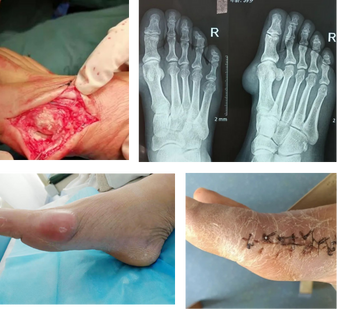

痛风石破溃且腐蚀关节,治疗后行走自如

患者:李应春

病情:全身多处巨大痛风石且破溃,已无法行走。

治疗:经过2次手术治疗,取出全部痛风石,修复骨关节,配合调理肾代谢,直至完全康复。